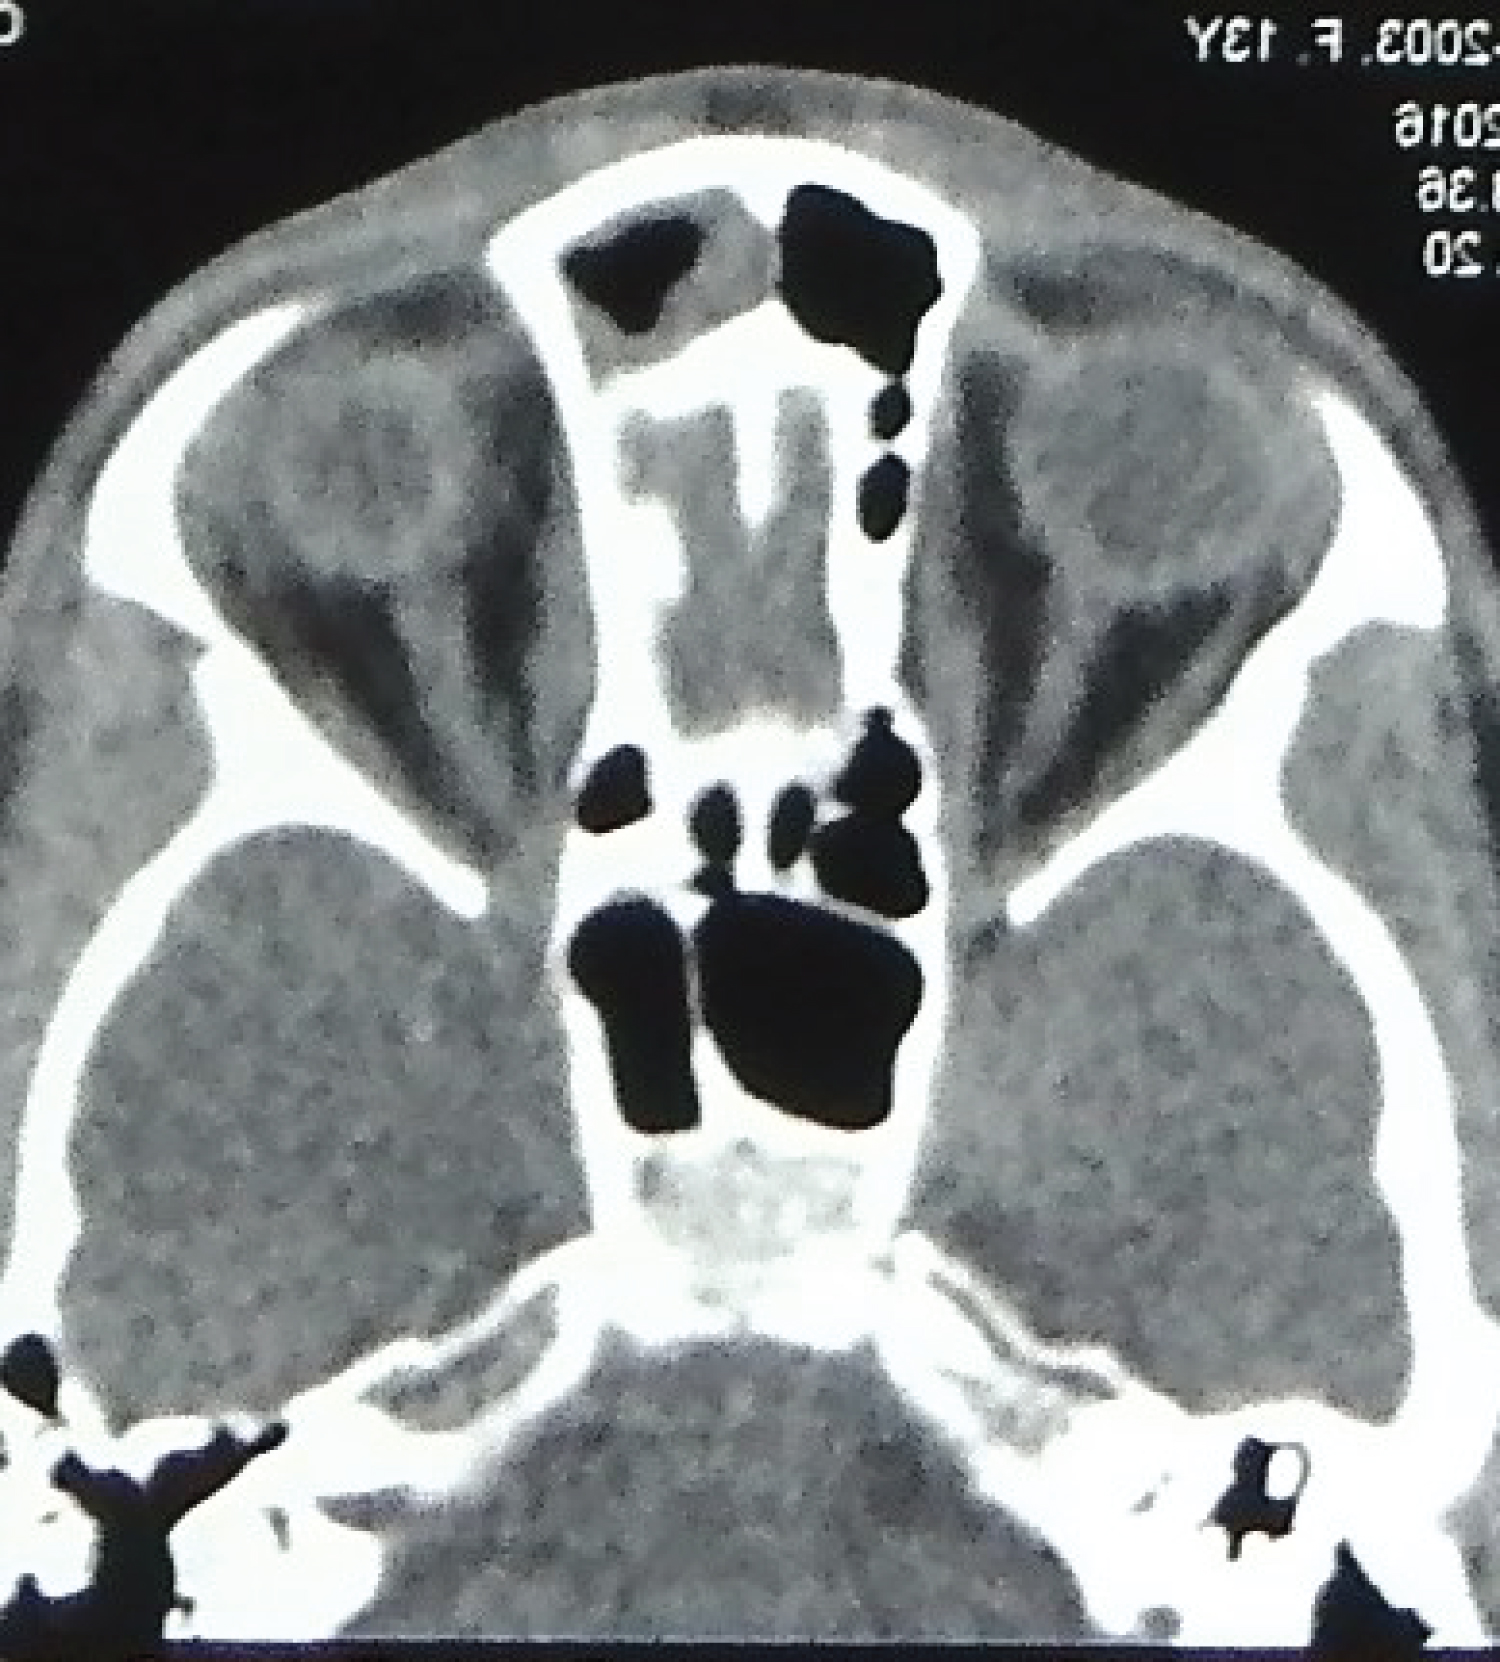

The swelling was non tender, smooth, diffuse, globular, not adherent to skin, the deeper margins were insinuated between the nasal bones. There were no signs of inflammation. A midline punctum was noted. A provisional diagnosis of NDSC was made. Contrast enhanced computed tomography (CECT) of head and neck was done. CECT scan detected a small volume of fluid along the nasal dorsum (Figure 3). There was no evidence of bony erosion along anterior cranial fossa and crista galli appeared to be normal for the age (Figure 4).

Figure 3: Axial cut of CT scan, showing fluid collection on dorsum of nose. View Figure 3

Figure 4: Axial cut of CT scan, showing normal crista galli. View Figure 4